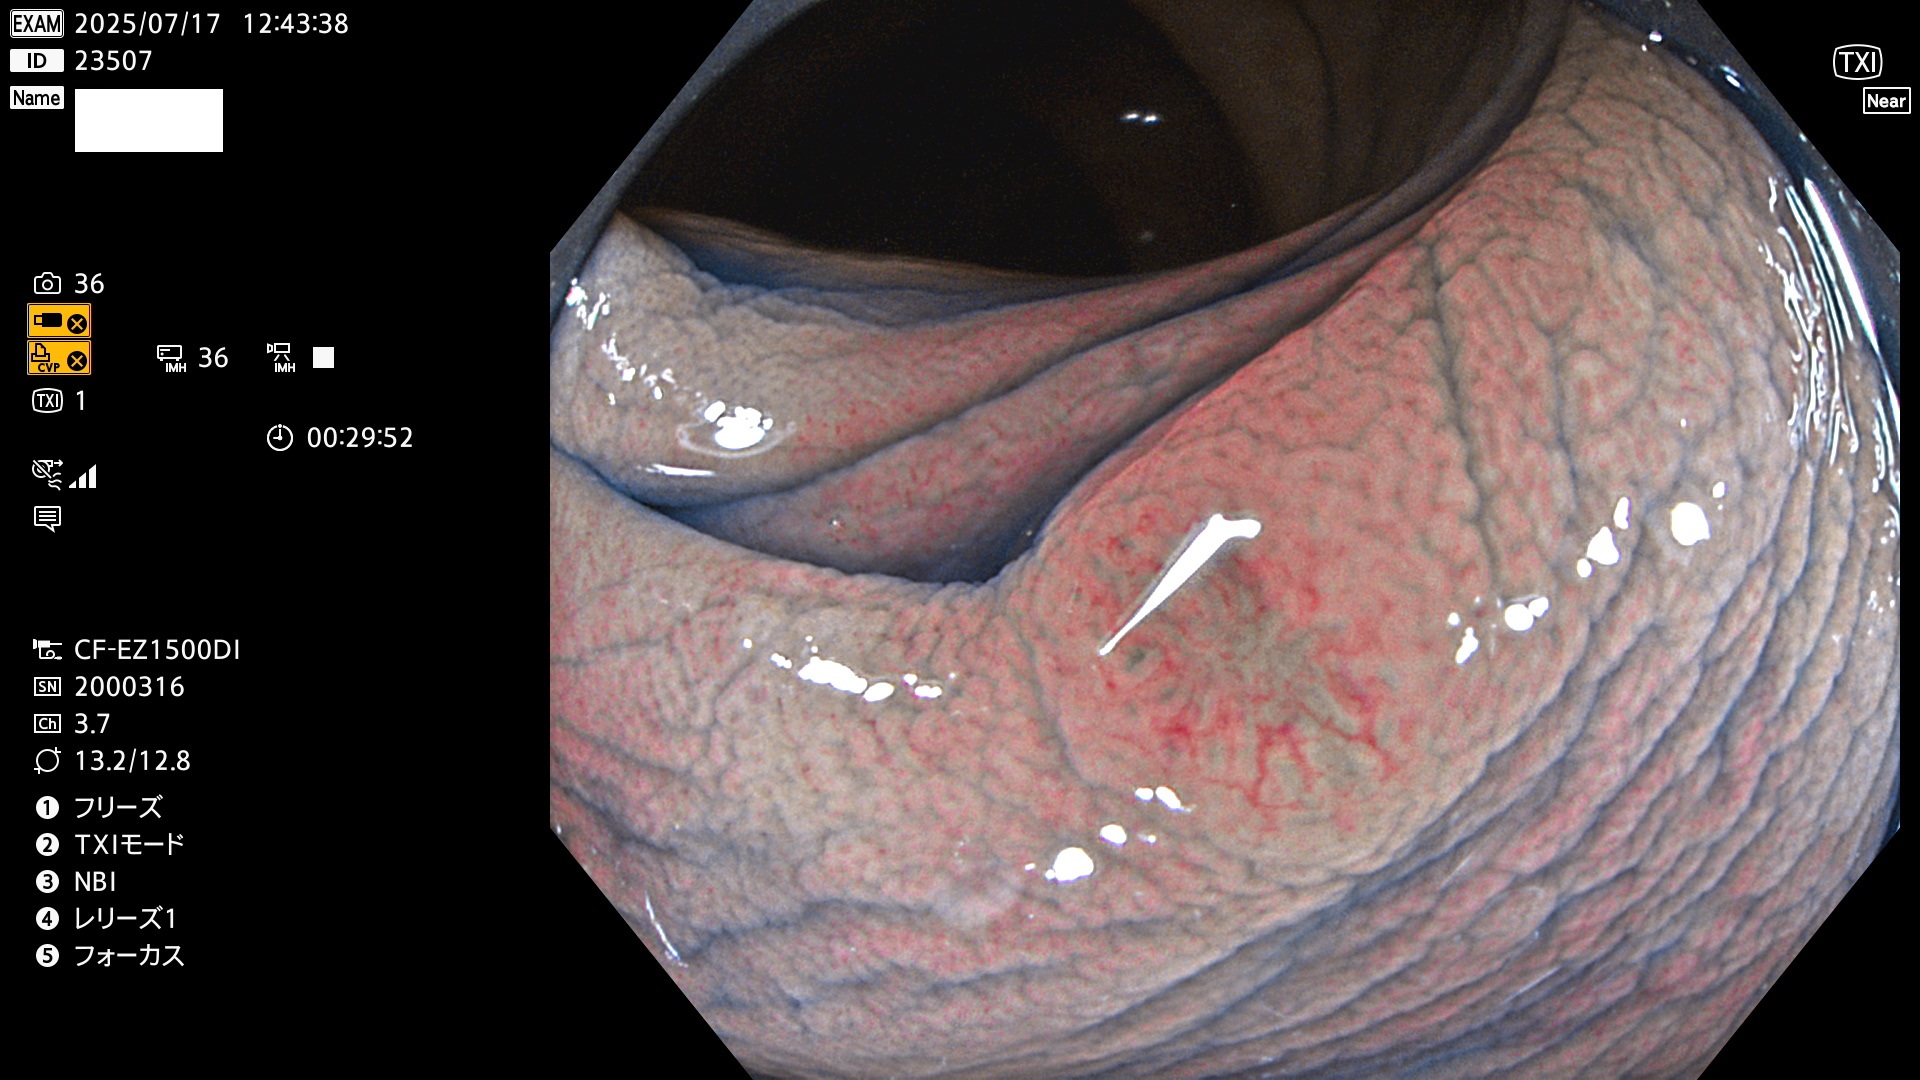

2025年7月17日〜7月20日の4日間(40件)8個 (Uc_ADR=8/40=20%)

びらん(炎症)と紛らわしいUc